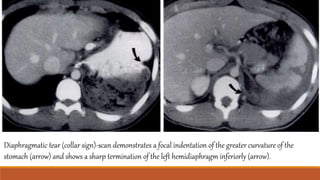

Diaphragmatic tear (collar sign)-scan demonstrates a focal indentation of the greater curvature of the

stomach (arrow) and shows a sharp termination of the left hemidiaphragm inferiorly (arrow).